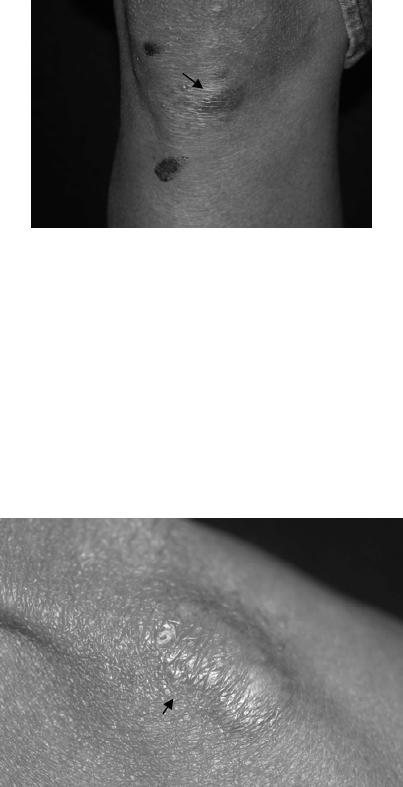

Figura 16: Granuloma micótico misto organizado polar com alta intensidade

dos elementos celulares (setas) e fungos (seta azul), em biópsia de lesão elevada. HE 20x.

Figura 17: Granuloma micótico misto organizado polar com baixa intensidade

dos elementos celulares e fungos (seta), em biópsia de lesão plana. HE 40x.

Figura 18: Imagem de GMMO polar de baixa intensidade Figura 19: Imagem de gigantócito contendo célula fúngica

em biópsia lesão plana. HE 40x. deteriorada em GMMO polar de baixa intensidade em

biópsia de lesão plana. HE 100x no original.

Figura 20: Imagem de GMMO polar de alta intensidade em biópsia de lesão elevada mostrando

eosinófilos, plasmócitos, linfócitos, macrófagos, células gigantes, neutrófilos e corpos escleróticos. HE 40x no original.

Figura 21: Imagem de GMMO polar de alta intensidade em biópsia de lesão elevada mostrando

infiltrado linfo-plasmocitário, com macrófagos, presente na periferia dos granulomas. HE 40x no original.

Figura 22: GMMO polar de baixa intensidade em biópsia de lesão plana. Figura 23: GMMO polar de alta intensidade em biópsia

HE 20x no aumento original. de lesão elevada com áreas de fibrose e vasculite. HE 10x.